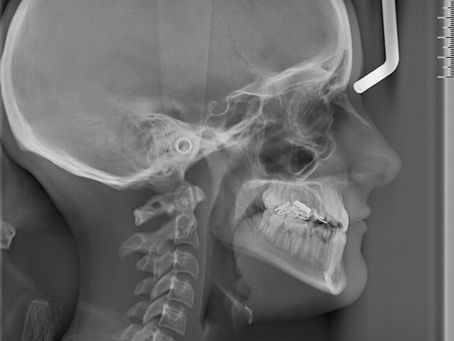

Sefalometri Filmi Nedir? Oran Çankaya Ankara’da Kullanım Alanları

Sefalometri filmi nedir? Oran Çankaya Ankara’da Funda Sarıkaya Ağız ve Diş Sağlığı Polikliniği’nde detaylı çene ve diş analizleri için sefal